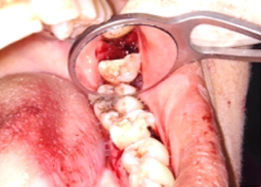

Hemisectomy

Post-OP Clinical View